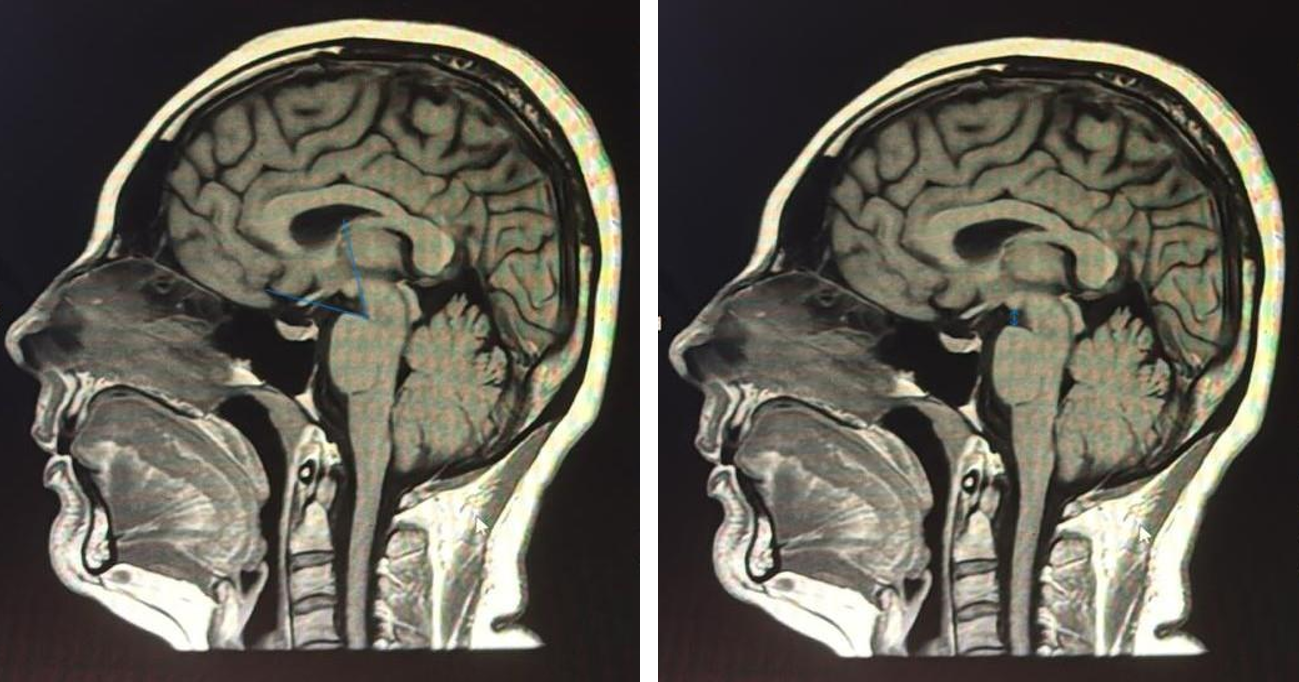

Tip 3 CVF: Embolizasyon ve Rebound

Vakalar 6 ve 7 (aynı hasta, iki yatış) CVF yönetiminin iki kritik ilkesini örneklemektedir. İlk yatışta dış merkezlerdeki EKY denemelerine yanıtsız Bern 9 olgu, BT miyelografi ile D2 hemiazigos CVF’si olarak tanımlanarak başarılı DSA embolizasyonu (Onyx) ile tedavi edildi; Pre- ve post-embolizasyon MRG görüntüleri Şekil 6’da sunulmaktadır.17,18 İkinci yatışta embolizasyon sonrası rebound intrakraniyal hipertansiyon, sekonder Chiari morfolojisi ve komünikan hidrosefali gelişti; posterior fossa dekompresyonu ve V/P şant gereksinimi oldu. Bu komplikasyon CVF tedavisi sonrasında aktif radyolojik izlemin kritik önemini vurgulamaktadır.